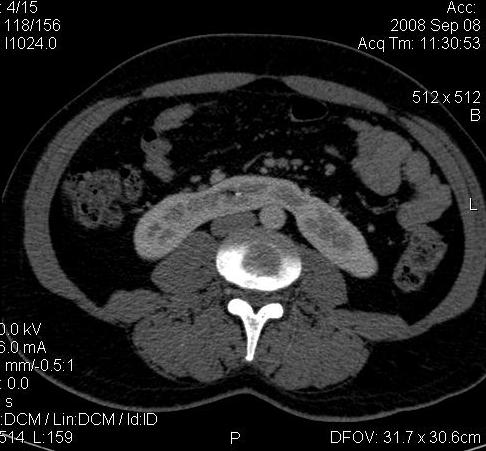

КТ Почек- подкова и уретеролитиаз

Ну ладно, раз никто больше не хочет, то отвечу свою версию - аномалия развития - подковообразная почка (horseshoe kidney).

Да красивая подковообразная почка - встречала раз 6-7.

Не вызывает сомнений. Картинка замечательная. Должно быть хорошо видно и на УЗИ.

Почечная колика; на последнем аксиальном скане чётко виден мелкий (2 мм) камень в устье правого мочеточника.

Для невладеющего КТ,очень четка видна аномалия на 3-4х снимках.А вот на 4-м скане в проксим.сегменте цистоида тоже есть гиперденсное точечное образование-не камень случайно?